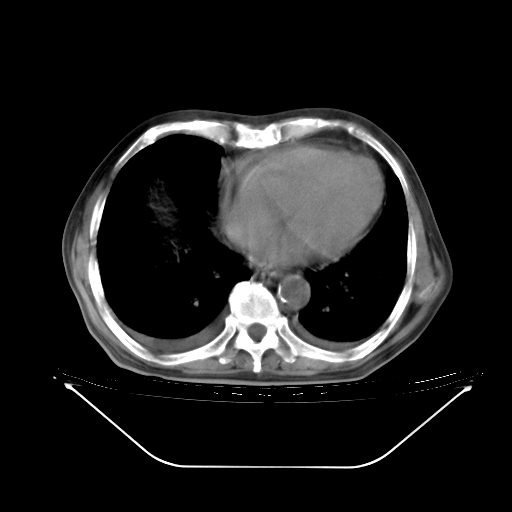

胸腹部CT,诊断意见:左上肺叶钙化灶、左侧胸膜局限性增厚并钙化、胆囊炎。描述部分肺组织呈磨玻璃样改变。